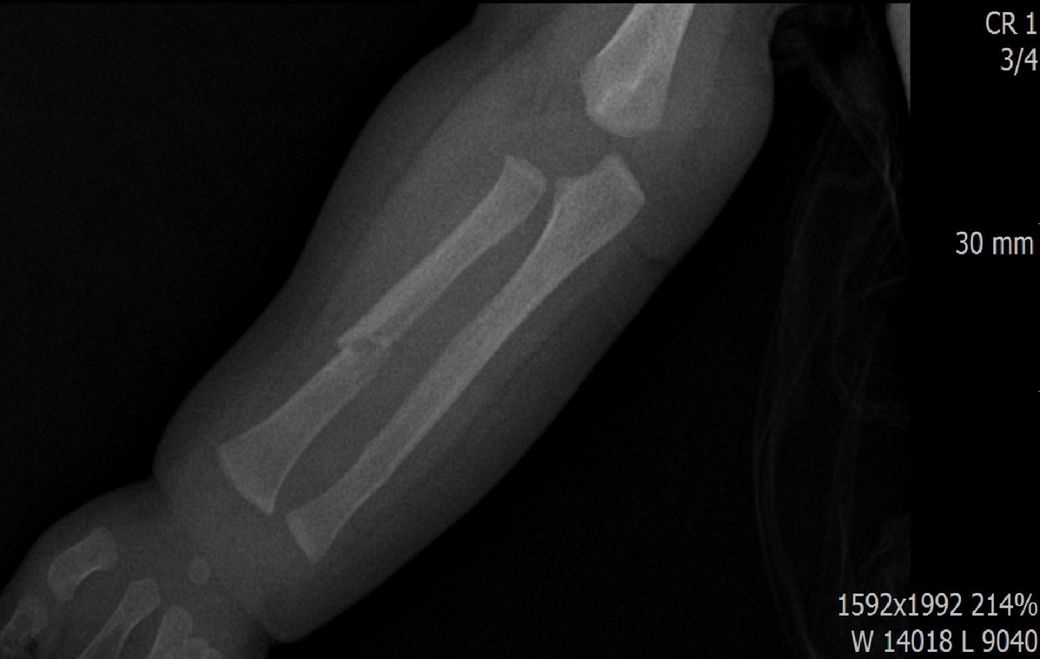

다름이 아니라, 첨부드린 엑스레이(X-ray) 사진처럼 골절 사실을 알게 되고 골절 발생 시점 대략적으로나마 추정시기를 파악하려고 문의 드리게 되었습니다

1) 3월 30일 촬영한 X-ray만으로 정확한 골절 시기를 100% 특정하는 데에는 한계가 있다는 점 충분히 인지하고 있기에 촬영날짜 기준으로 대략적으로 어느정도 시점에서 발생되었을 것으로 추측(ex 당일, 7~10일전, 7~14일 전, 10일 ~ 20일전, 14일 ~ 30일전 등등등)되는지 이해하고 싶습니다.

• 2번 째 사진

하지만, 아예 불가능한건 아니고 골절선이 얼마나 뚜렷하냐, 골막 반응이 보이느냐, 연골성 가골 형성이 있느냐 등으로 골절 시기를 추정해볼 수 있습니다.

골절선이 뚜렷하면 0~1주, 골막 반응이 시작되면 1~2주, 연골성 가골이 형성되기 시작하면 2~3주, 가골이 명확해지면 3~6주 정도로 추정할 수 있습니다.

골절선이 흐려졌고 가골이 형성되기 시작하는 2~3주경이 아닌가 의심이 되지만 제가 골절을 주로 보는 정형외과 전문의가 아니라서 정확도가 떨어집니다.